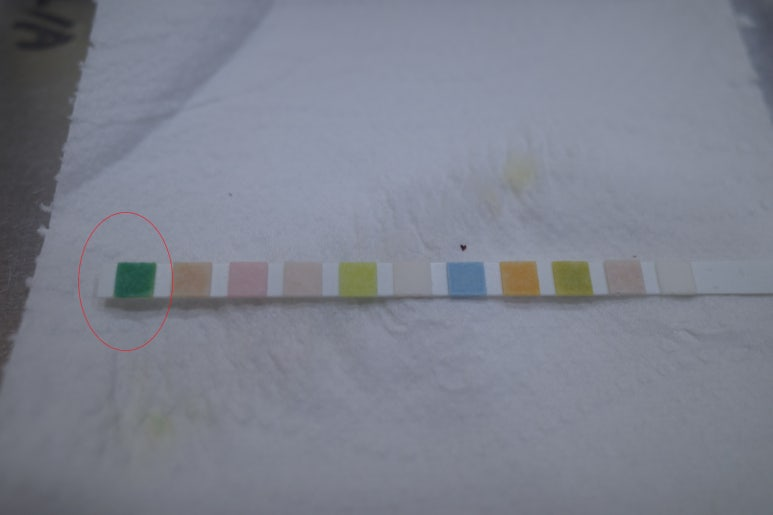

40대 중반 여자, 본원에서 혈압약 투약중 백의 고혈압도 약 15 정도 있는 것으로 판단... 병원에서 긴장하는 타입 전농동 의원에서 근무중 2일전부터의 증상으로 내원 열이 나고... 오한이 심했고... 39도까지 (응급실 갈까...고민) 다음날 바로 근무처 같은 건물의 내과 (아래 사례의 병원) 갔었고...위장약??을 받았다 https://blog.naver.com/ejercicio/223777862276 ; 약먹고 울렁거려서 중단 --> 결국 아래에 고려한 요로감염의 증상으로 봐야하지 않을지? 비전형적인 신우신염, 폐혈증; 구토가 주증상 이었던 https://blog.naver.com/ejercicio/221705668093 어제는 밤에 미열 ; 화장실을 자주 간다. 한시간에 한번.. ?? 근무중 자주가는 느낌은 맞다 ( 참지못하고 ). 방광염을 언급/생각하였다는, 소변 증상은 약한거 같고... 고열이 있었다면 단순 방광염을 초과